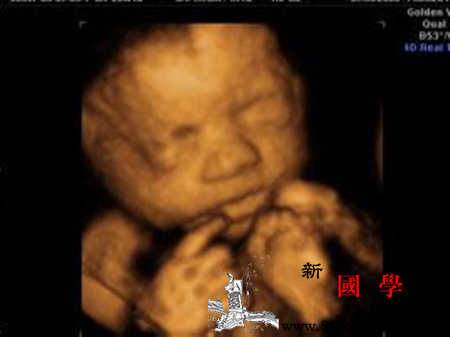

核心提示:其实生小孩一直都不是一个人的事,孩子是两人爱的结晶,而分娩痛却只能由一个人承受,那种生宝宝的痛楚只有有孩子的妈最知道,但现在研究指出,有个贴心老公这些一举一动,可有效降低疼痛指数!一、分娩前的征兆有哪些?孕妇临产前征兆之一孕妇在分娩发动前,常出现假临产。假临产的特点是:①宫缩时间短且不恒定,间歇时间长且不规律,宫缩强度不增加;②宫缩时宫颈管不缩短③常在夜间出现,清晨消失④给与强镇静药物能抑制宫缩。孕妇临产前征兆之二多数孕妇自觉上腹部较前

大多数孕妇在临产前24-48小时内(少数一周内),因宫颈管内口附近的胎膜与该处的子宫壁剥离,毛细血管破裂有少量出血并与宫颈管内粘液栓相混,经阴道排除,称之为见红,是分娩即将开始比较可靠的征象。